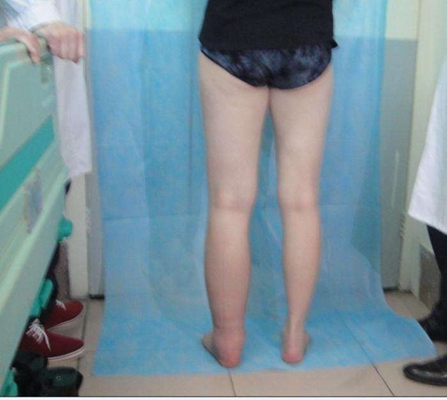

妊娠水腫圖片

浮腫圖 (8)

浮腫圖 (7)

浮腫圖 (7)

浮腫圖 (6)

浮腫圖 (5)

浮腫圖 (6)

浮腫圖 (5)